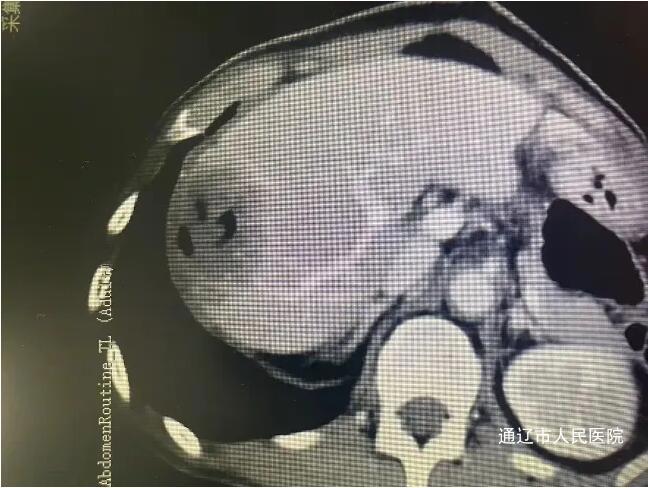

近日,我院肝胆胰外科成功实施了全市首例CT引导下肝肿瘤纳米刀消融术,标志着我院肝胆胰外科在肿瘤微创消融领域迈上新台阶,填补了本地区医疗技术空白。该患者男性,因腹胀于我院就诊,完善相关检查诊断结肠癌伴肠梗阻,肝占位性病变考虑转移瘤,讨论病情后决定一期行腹腔镜下根治性右半结肠切除术,术后复查腹部增强CT、增强肝脏MRI提示肝脏转移瘤有进展趋势,遂行CT引导下肝肿瘤纳米刀消融术。

手术过程中,患者行全身麻醉,在解放军总医院肖越勇教授指导下,我院肝胆胰外科主任医师郭雅明、手术麻醉科副主任医师高飞、CT室医护团队在CT引导下确认病灶位置并进针,确保电极区域完全包裹肿瘤后开始消融。消融过程中电流上升反馈良好,术后即刻增强CT显示消融范围覆盖病灶,周围血管、胆道结构完好无损伤,出现明显气体影,消融效果良好。消融完成后,退出穿刺针,手术顺利结束,术中麻醉效果满意,生命体征平稳,麻醉恢复后无腹痛腹胀,恶心呕吐等不适。术后给予对症支持治疗,患者恢复良好。和传统的消融治疗方式不同,纳米刀消融技术是通过脉冲电场导致细胞不可逆电穿孔,从而实现肿瘤组织杀伤,是一种非热选择性物理消融技术,可在实现消融肿瘤的同时,保留肿瘤周围的重要管道结构(血管、胆管和神经)完整性,并且无热沉效应,消融肿瘤细胞,适用于消融治疗靠近肝门、胆囊、膈肌和结肠等肝脏特殊部位的肿瘤有着独特的优势。纳米刀消融手术为现阶段先进、安全的肿瘤消融技术,它为无法使用传统手术方式的特殊部位癌症患者提供了新的治疗方式,还具有能够选择性消融,时间短、创口小等优点,一定程度上能够改善生活质量,延长生存时间,纳米刀消融对不能手术的肝癌、肺癌特别是胰腺癌具备较大的技术优势。此次全市首例纳米刀消融术的开展,标志我院微创介入技术取得重大突破,也为疑难肿瘤患者提供了更为先进技术的诊疗手段。